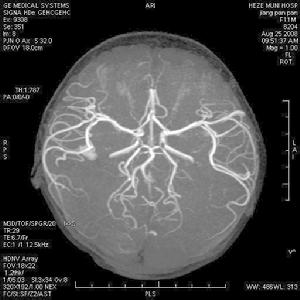

(三)蛛網膜下腔出血(subarachnoid hemorrhage)可迅速出現一種類似柯薩可夫精神病的表現,患者有定向障礙,這類遺忘綜合徵常於數日或數周后的無症狀間歇期後發生,歷時短暫,多於數周后很快恢復。根據其突發劇烈頭痛、嘔吐、腦膜刺激征陽性,腰穿腦脊液均勻血性可確診。

(六)腦動脈硬化性精神障礙(mental disorders caused by cereboar teriosclerotic)患者可表現情感障礙、意識障礙、人格障礙及記憶障礙等。早期以近記憶障礙為主,以後視覺性、聽覺性記憶也有明顯減退,晚期遠記憶減退較明顯,並可產生遺忘症、虛構等。此類患者常有些神經系統症狀和體徵。腦血流圖較有價值。